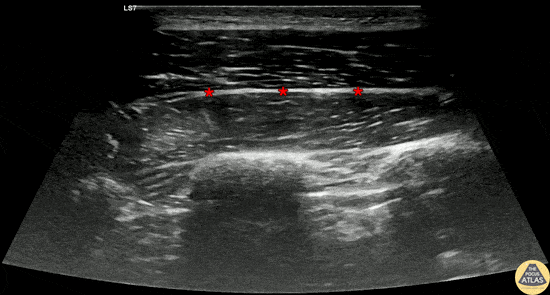

30s M presented with atraumatic acute onset chest pain in the context of inhaled marijuana use, and was found to have a spontaneous pneumothorax. The patient was hemodynamically stable, so a serratus anterior plane block was performed for analgesia and to facilitate pigtail chest tube placement. The block is shown here, with the fascial plane (*) between the serratus anterior muscle (deep) and latissmus dorsi (superficial). This block was performed using an out-of-plane approach, depositing anesthetic in to the fascial plane. This patient had mixed analgesic efficacy and so required additional anesthetic for chest tube placement, and was then admitted for further management. Dr. Cody Brevik, PGY4, Denver Health Residency in Emergency Medicine Dr. Nimish Bhatt, Fellow, Denver Health Ultrasound Fellowship